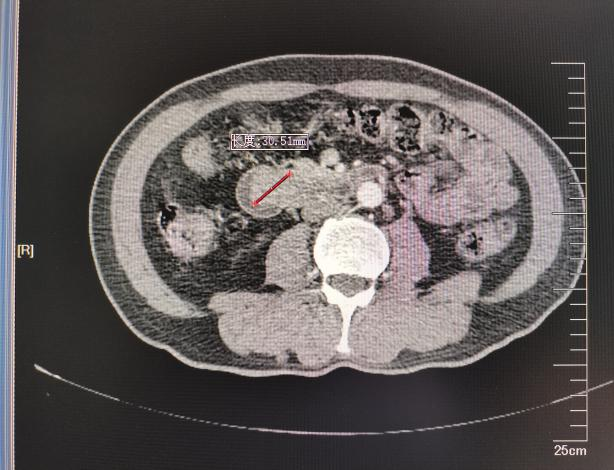

入院后查血提示肝功能异常,胆红素高达122.1 umol/L。腹部增强CT、增强MR+MRCP均提示:胆总管下段、十二指肠乳头区占位,考虑壶腹癌;低位胆道梗阻,肝内外胆管、胰管扩张。行胃十二指肠镜检查示:十二指肠降段肿物。这些检查结果显示:患者的黄疸症状为壶腹部肿瘤压迫堵塞胆管,胆汁流出受阻所致。

患者术前肝功能较差并且影像学检查显示:血管存在解剖学变异,右肝动脉由肠系膜上动脉发出,这些因素均增加了手术的风险与难度。